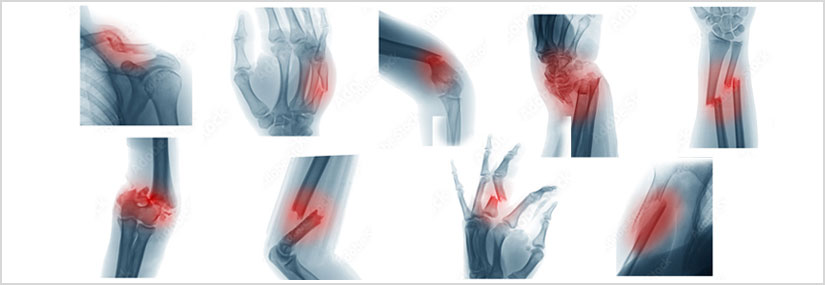

Upper Limb Fractures

Upper limb fractures are breaks or cracks in the bones of the upper limb, which includes the shoulder, arm, forearm, wrist, and hand. These fractures can occur due to trauma, falls, sports injuries, or other accidents. The specific type of fracture and the bone affected can vary widely, each requiring different treatment approaches.

Types of Upper Limb Fractures